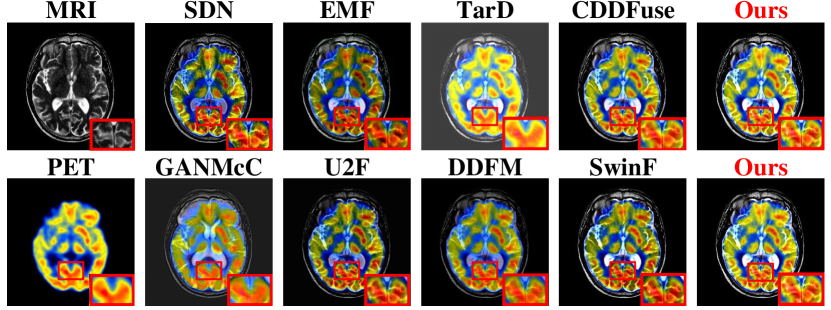

Refer to caption

Figure 7. Visual comparison for MRI-PET MIF dataset.

In this section, MambaDFuse is compared with the state-of-the-art methods, including the CNN and AE-based methods group: SDN (Zhang and Ma, 2021), EMF (Xu and Ma, 2021), U2F (Xu et al., 2020a); and the generative methods group: GANMcC (Ma et al., 2020b), TarD (Liu et al., 2022), DDFM (Zhao et al., 2023b); and the Transformer-based methods group: CDDFuse (Zhao et al., 2023a), SwinF (Ma et al., 2022). Among them, EMF is an architecture designed specifically for the MIF task, so it is not compared in the IVF task.

Qualitative comparison. Subsequently, we show the qualitative comparison in Fig. 5, 6 and 7. MambaDFuse effectively integrates thermal radiation information from infrared images with detailed texture and illumination information from visible images. Consequently, objects located in dimly-lit environments are conspicuously accentuated, enabling easy distinguishing of foreground objects from the background. Moreover, previously indistinct background features due to low illumination now possess clearly defined edges and abundant contour information, enhancing their ability to comprehend the scene.